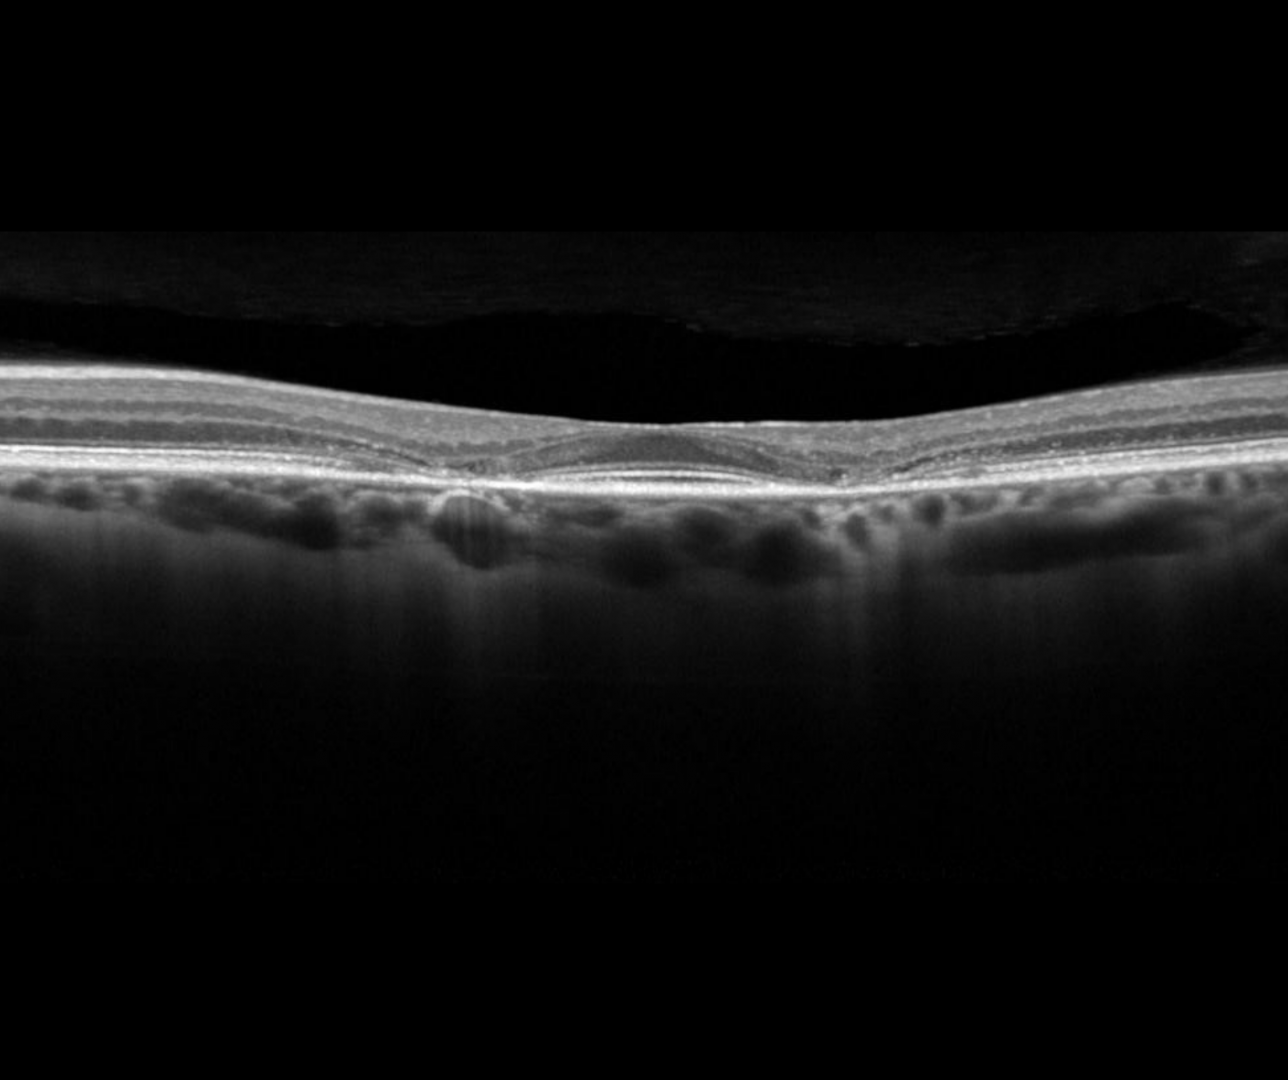

OCT imaging shows disruption of the parafoveal ellipsoid zone in the early stages. In later stages, the outer retinal layers can be involved. A ‘flying saucer’ sign may be seen on an OCT line scan which describes preservation of the subfoveal layers but perifoveal loss of the ellipsoid zone (EZ) on either side.

More infoSpectralis OCT volume and line scans (right eye)

More infoSpectralis OCT volume and line scans (left eye)